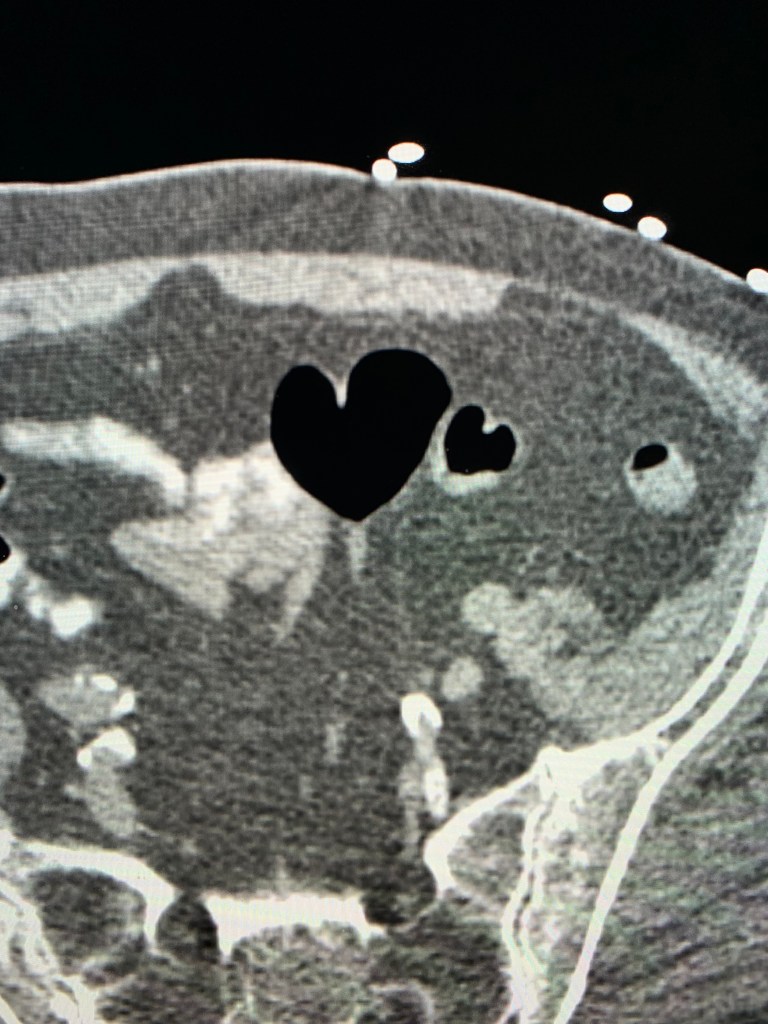

Axial CT image of the abdomen shows two heart-shaped foci of gas within the sigmoid colon